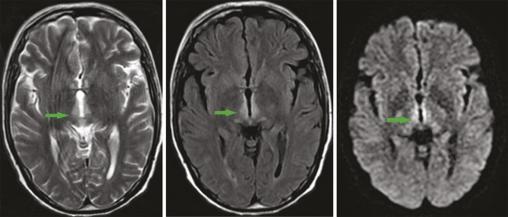

Ce patient de 49 ans, ayant bénéficié d’une duodénopancréatectomie céphalique pour un ampullome vatérien, était admis pour des vomissements incoercibles apparus en postopératoire immédiat, rebelles au traitement, et mis sous nutrition parentérale. Une semaine plus tard apparaissait un syndrome confusionnel avec apathie et hypersomnie. L’imagerie par résonance magnétique (IRM) montrait des hypersignaux T2, Flair et diffusion, bilatéraux et symétriques du thalamus postéromédian, périventriculaires du troisième ventricule et périaqueducaux en hypersignal (fig. 1, 2 et 3 ). Devant cet aspect en imagerie, associé aux vomissements prolongés, à l’alimentation parentérale et aux troubles neuropsychiques, une encéphalopathie de Gayet-Wernicke était évoquée, et le patient mis sous thiamine, avec une bonne évolution.

L’encéphalopathie de Gayet-Wernicke est une urgence médicale due à une carence aiguë et massive en vitamine B1.1 En dehors de l’alcoolisme, ses facteurs de risque sont : chirurgie gastro-intestinale, vomissements chroniques, nutrition parentérale prolongée, jeûne prolongé, malnutrition, anorexie mentale, chimiothérapie, sida.2 Elle se manifeste par une triade associant à divers degrés des troubles neuropsychiques (confusion, apathie, bradypsychie, hypersomnie), des troubles oculomoteurs et des troubles de l’équilibre. L’IRM cérébrale objective classiquement des hypersignaux symétriques dans les séquences pondérées T2, Flair et parfois une diffusion, de part et d’autre du troisième ventricule, des noyaux thalamiques postéromédiaux, des corps mamillaires, et de la région périaqueducale.1 Son traitement est fondé sur l’administration de thiamine.